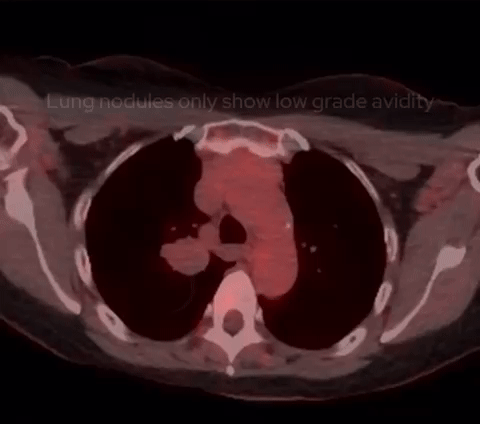

Next came a PET-CT scan. While the lung nodules showed only mild FDG avidity, areas within both breasts exhibited more significant avidity. This prompted a referral to the breast unit for further investigation. The breast lesions turned out to be benign papillomas, unrelated to the lung nodules.

PET-CT shows only low grade FDG avidity within the lung nodules with high FDG avidity within several bilateral breast nodules, subseuqnetly worked up and found to represent benign papillomas.